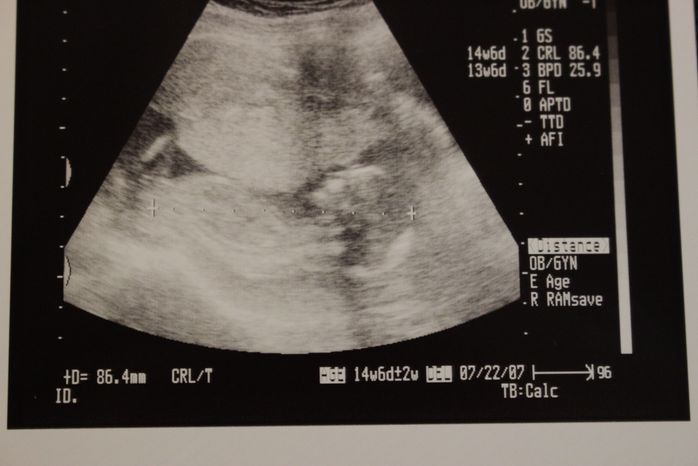

妊娠14週目のエコー写真

なんと人の顔らしきものと背骨が見えます。「ぽん太」という愛嬌あるネーミングにそぐわない端正な顔立ち・・・と早くも親バカを楽しみ始めた頃です。つわりと一日中襲ってくる眠気との闘いを支えるモチベーションになっていました。